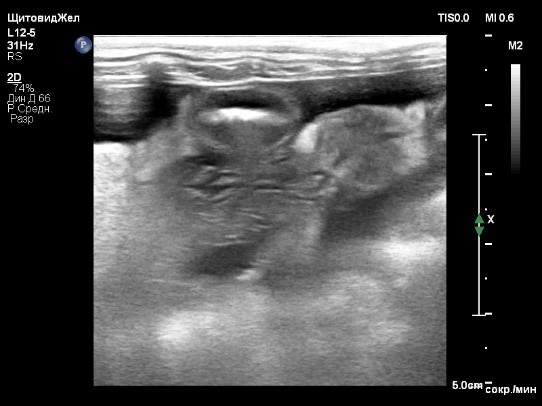

Были проведены лабораторные исследования крови, включающие биохимический и клинический анализы. В результате проведения биохимического анализа было выявлено умеренное повышение гепатоцеллюлярных ферментов (табл. 1), в то время как результат клинического анализа показал легкую анемию без признаков регенерации. Дополнительно были измерены уровни желчных кислот методом парных проб (до и после кормления). Результаты показали выраженное повышение, что свидетельствует о синтетической дисфункции печени (табл. 2). Уровень глюкозы в крови составил 3,4 ммоль/л при норме 3,5–6,1 ммоль/л, что указывает на наличие легкого уровня гипогликемии.Ультразвуковое исследование органов брюшной полости выявило признаки микрогепатии, нефролитиаза, уролитиаза и асцита (скопление жидкости в брюшной полости) в небольшом количестве (до 2 мм на просвет; фото 1).